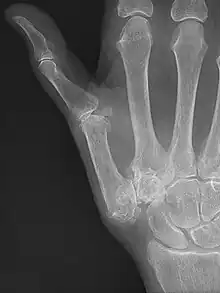

Trapeziometacarpal osteoarthritis (TMC OA) is, also known as osteoarthritis at the base of the thumb, thumb carpometacarpal osteoarthritis, basilar (or basal) joint arthritis, or as rhizarthrosis.[3][1][2] This joint is formed by the trapezium bone of the wrist and the metacarpal bone of the thumb. This is one of the joints where most humans develop osteoarthritis with age.[4] Osteoarthritis is age-related loss of the smooth surface of the bone where it moves against another bone (cartilage of the joint).[3][5] In reaction to the loss of cartilage, the bones thicken at the joint surface, resulting in subchondral sclerosis. Also, bony outgrowths, called osteophytes (also known as “bone spurs”), are formed at the joint margins.[6]

TMC OA is diagnosed based on symptoms and signs.[8] Radiographs can confirm the diagnosis and the severity of TMC OA. Other diagnoses in this region include scaphotrapezial trapezoid arthritis and first dorsal compartment tendinopathy (De Quervain syndrome) although these are usually easy to distinguish.

TMC OA severity was classified by Eaton and Littler which can be simplified as follows:[21][22]

Stage 1:

- slight widening of the joint space

- < 1/3 subluxation of the joint (in any projection)

Stage 2:

- Osteophytes, < 2 mm in diameter, are present. (usually adjacent to the volar or dorsal facets of the trapezium)

Stage 3:

- Osteophytes, > 2 mm in diameter, are present (usually adjacent to the volar and dorsal facets of the trapezium)

- Slight joint space narrowing

Stage 4:

- Narrow joint space

- Concomitant scaphotrapezial arthritis

A simpler classification is no arthritis, some arthritis, and severe arthritis.[23] This simpler classification system omits the potentially contradictory details of the Eaton/Littler classification and keeps scaphotrapezial arthrosis separate.